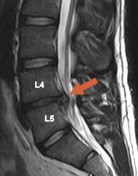

Samotné zvýšení rozsahu pohyblivosti souvisí i se zvýšenou mechanickou iritací daného úseku (segmentu) na úrovni disků, ligament, kloubních pouzder, nervových kořenů a jejich obalů. Samotné řešení akutní herniace disku je v prvé řadě spojeno s klinickým a radiologickým vyšetřením. RTG snímky nejsou pro potvrzení výhřezu dostatečné. Metodu první volby představuje MR – magnetická resonance, která je schopna rozlišit i staré jizvy od čerstvé recidivy (viz obr. 3). Případnou formu vyšetření představuje CT

Obr. 3.: MR: Výhřez ploténky v segmentu L4-L5 (zdroj: sr.wikipedia.org)